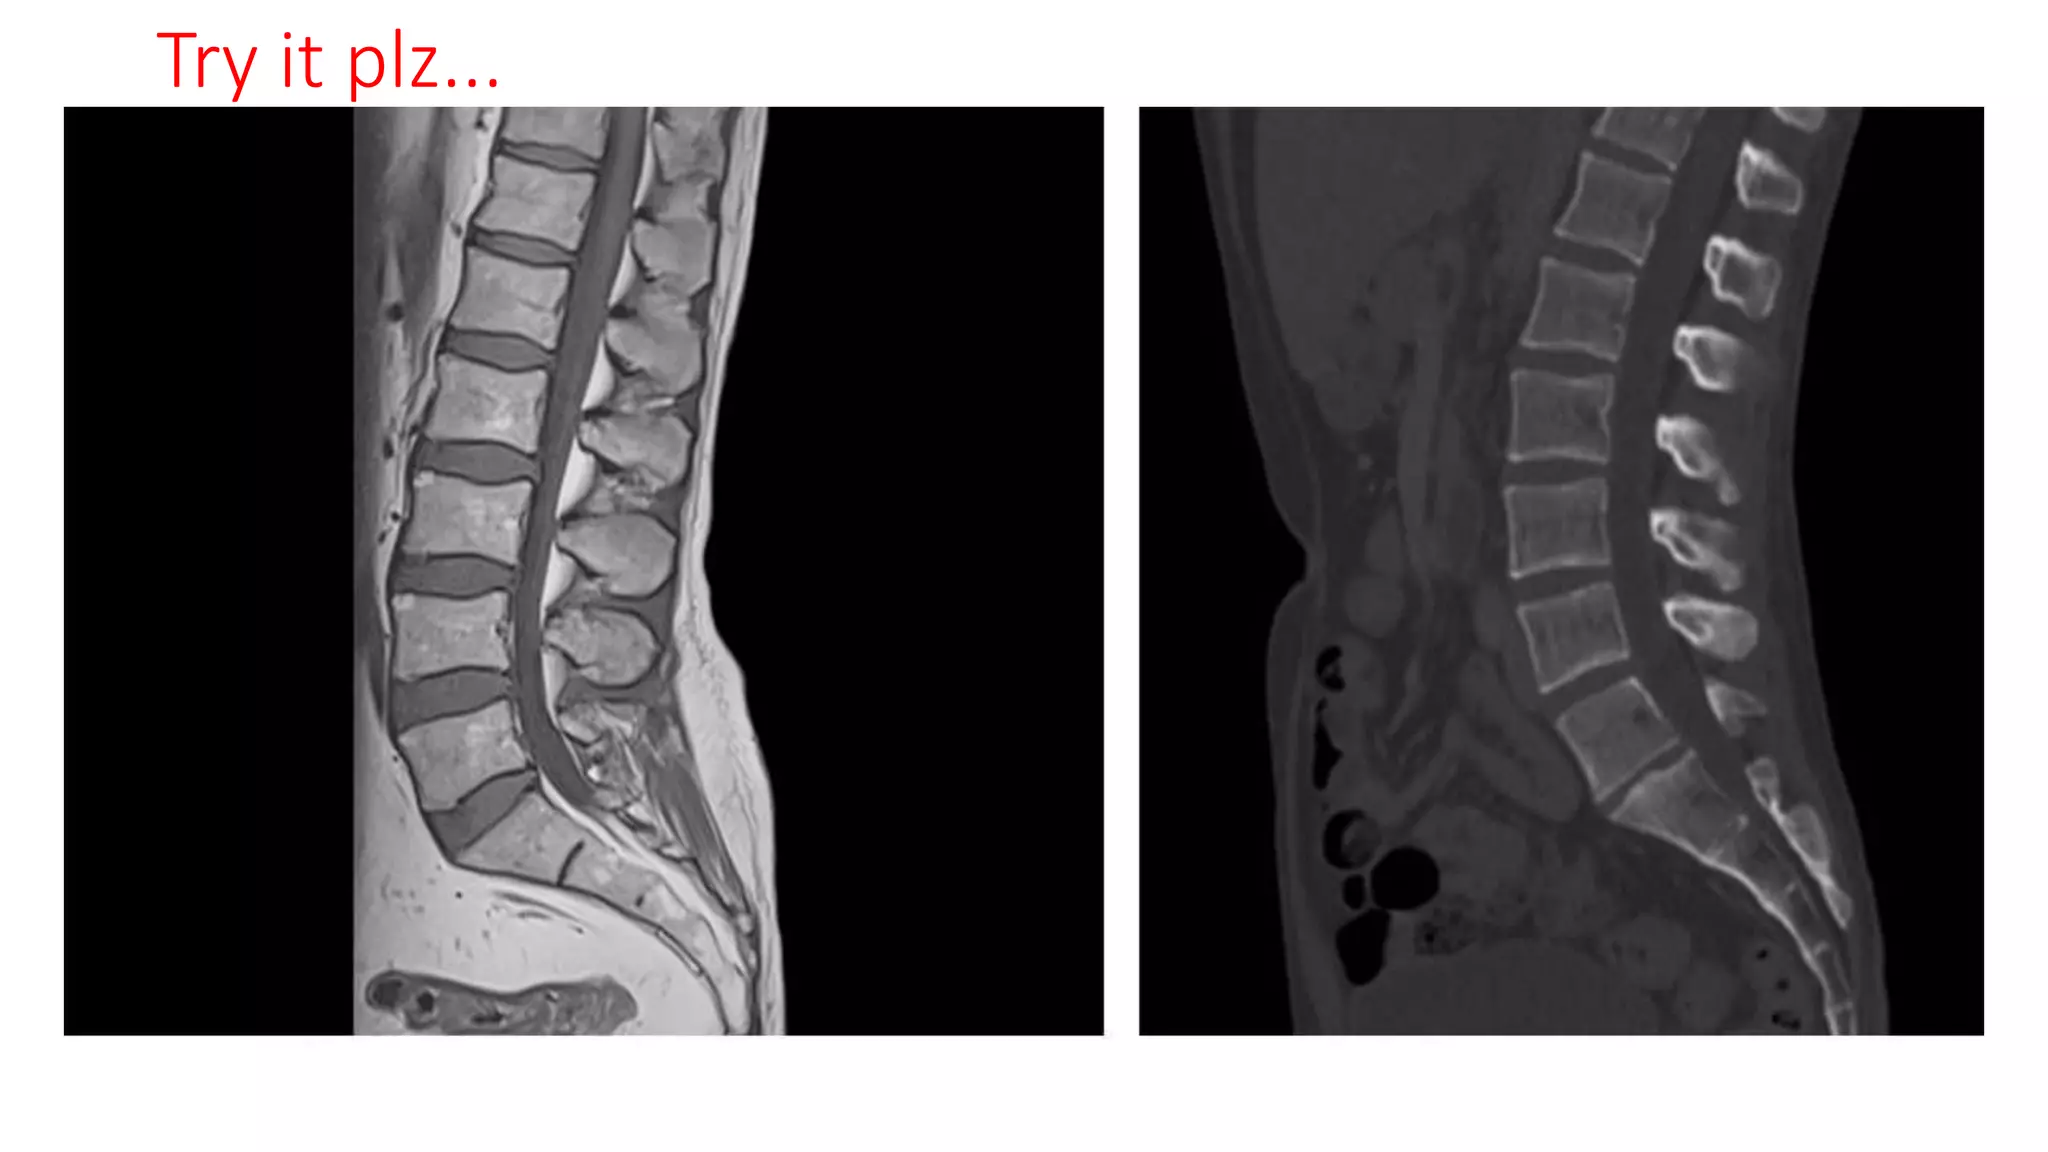

The document is an introductory guide to radiology by Dr. Mathew Joseph, covering the stages of investigations and various imaging techniques, both ionizing and non-ionizing. It outlines the principles of radiology and properties of X-rays, as well as contrast radiography and its applications. The document serves as a foundation for further region-wise radiology classes.